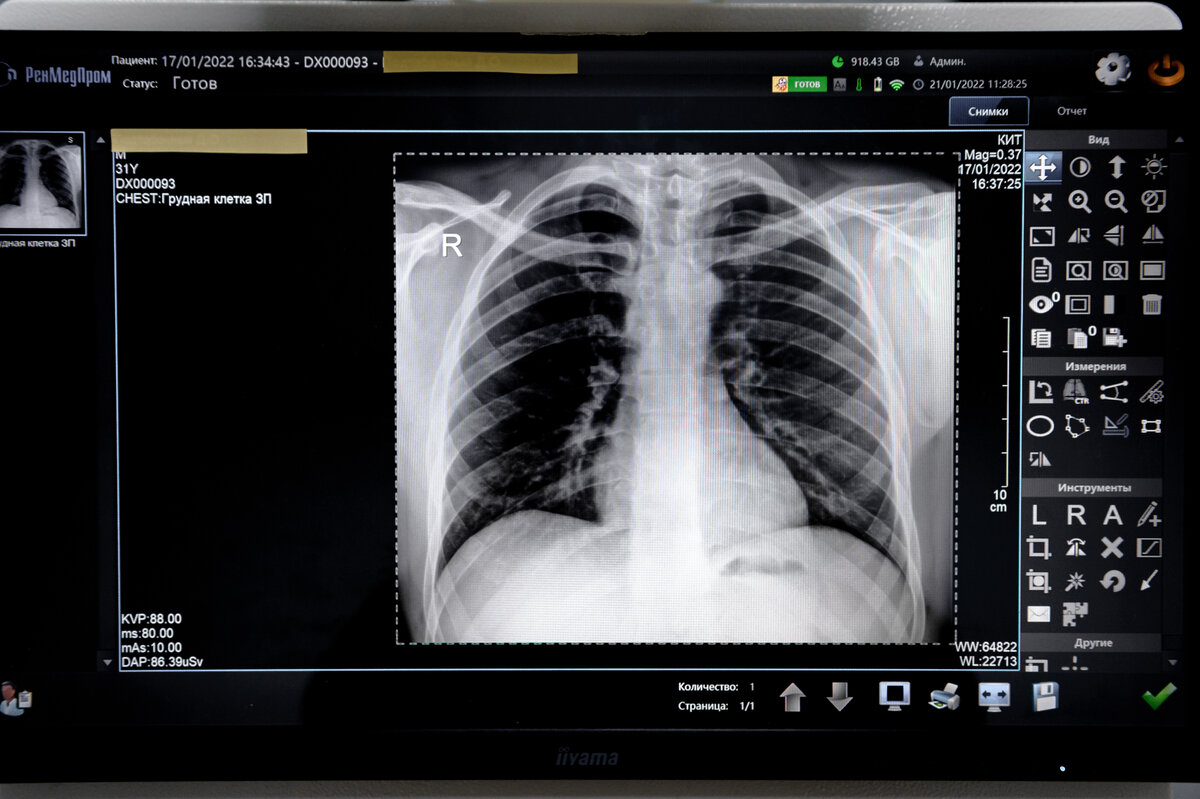

Рентген был открыт почти 130 лет назад (его автор — известный немецкий физик и нобелевский лауреат Вильгельм Конрад Рентген), но этот метод диагностики по-прежнему считается одним из самых популярных! С его помощью проводится обследование легких и успешно диагностируются травмы.

• Кости практически полностью поглощают рентгеновские лучи, мягкие ткани задерживают их частично, а воздух полностью пропускает, поэтому на снимках мы видим тени разной интенсивности.